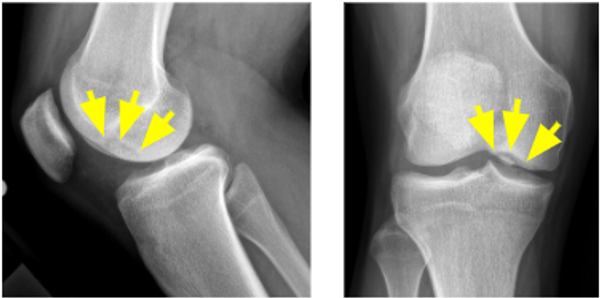

5. What is this lesion called on the x-ray views of the knee?

Correct Answer: Osteochondritis dissecans

This image shows an tunnel/notch and lateral x-ray views of the knee that demonstrate an osteochondritis dissecans (OCD) lesion of the lateral aspect of the medial femoral condyle.

OCD is a condition that develops in joints in children and adolescents. It occurs when a small segment of bone begins to separate from its surrounding region due to a lack of blood supply. As a result, the small piece of bone and the cartilage covering it begin to crack and loosen.

The most common joints affected by osteochondritis dissecans are the knee, ankle and elbow, although it can also occur in other joints. The condition typically affects just one joint; however, some children can develop OCD in several joints.

In many cases of OCD in children, the affected bone and cartilage heal on their own, especially if a child is still growing.

In grown children and young adults, OCD can have more severe effects. The OCD lesions have a greater chance of separating from the surrounding bone and cartilage and can even detach and float around inside the joint. In these cases, surgery may be necessary.